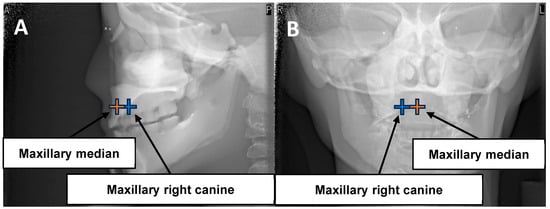

| This Study | Pauwels et al. [45] | |||||||

|---|---|---|---|---|---|---|---|---|

| Position | Maxillary canine | Maxillary median | Maxillary canine | Maxillary median | ||||

| Tube voltage (kV) | 90 | 90 | 90 | 90 | ||||

| Tube current (mA) | 3 | 3 | 5 | 5 | ||||

| FOV (cm) | 4 × 4 | 6 × 6 | 4 × 4 | 6 × 6 | ||||

| Rotation angle (°) | 360 | 180 | 360 | 180 | 360 | 180 | 360 | 180 |

| Exposure time (s) | 17.5 | 9.0 | 17.5 | 9.0 | 17.5 | 9.0 | 17.5 | 9.0 |

| Lens | 38.3 ± 0.00 | 14.1 ± 0.50 | 72.7 ± 0.49 | 26.1 ± 0.48 | 174 | 95 | 608 | 288 |

| Thyroid | 51.1 ± 0.49 | 25.0 ± 0.00 | 147.4 ± 0.95 | 72.4 ± 0.00 | 108 | 50 | 175 | 88 |

| Parotid gland | 225.4 ± 0.98 | 199.5 ± 0.50 | 326.3 ± 0.50 | 284.3 ± 0.48 | - | - | - | - |

| Sublingual gland | 67.7 ± 0.00 | 43.7 ± 0.45 | 456.7 ± 2.26 | 338.0 ± 0.00 | - | - | - | - |

| Salivary gland | - | - | - | - | 845 | 573 | 2192 | 1583 |